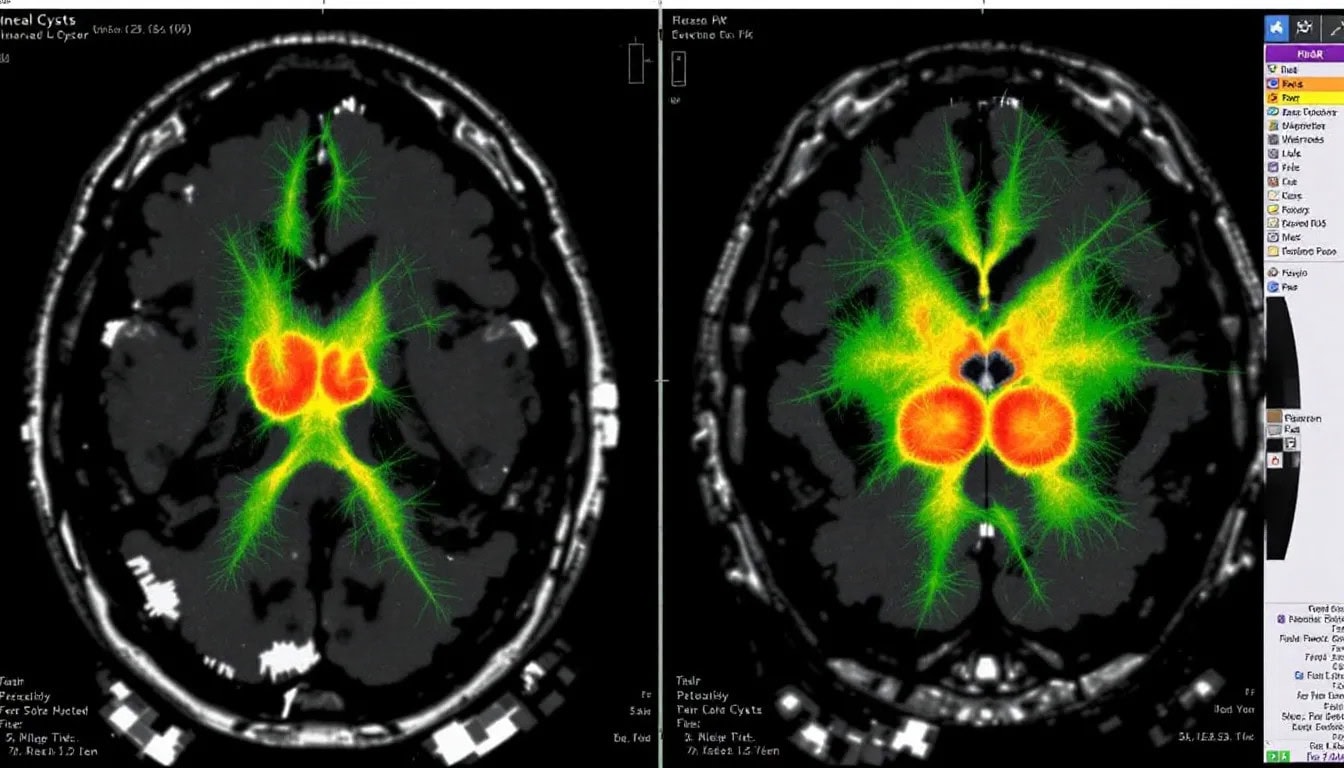

Diagnosing a pineal cyst typically involves imaging tests like CT scans and MRI. These scans reveal well-defined fluid density lesions on CT and homogeneous signals on MRI, with pineal cysts often appearing iso to hypointense on T1-weighted images. About 60% of pineal cysts demonstrate enhancement with contrast on T1-weighted imaging, providing additional diagnostic clarity. Nodular enhancement may indicate previous hemorrhage, which is an important detail for accurate diagnosis.

Pineal cysts are often discovered incidentally during imaging for unrelated issues. Regular imaging is crucial for monitoring the cyst’s stability and ensuring it does not lead to complications.